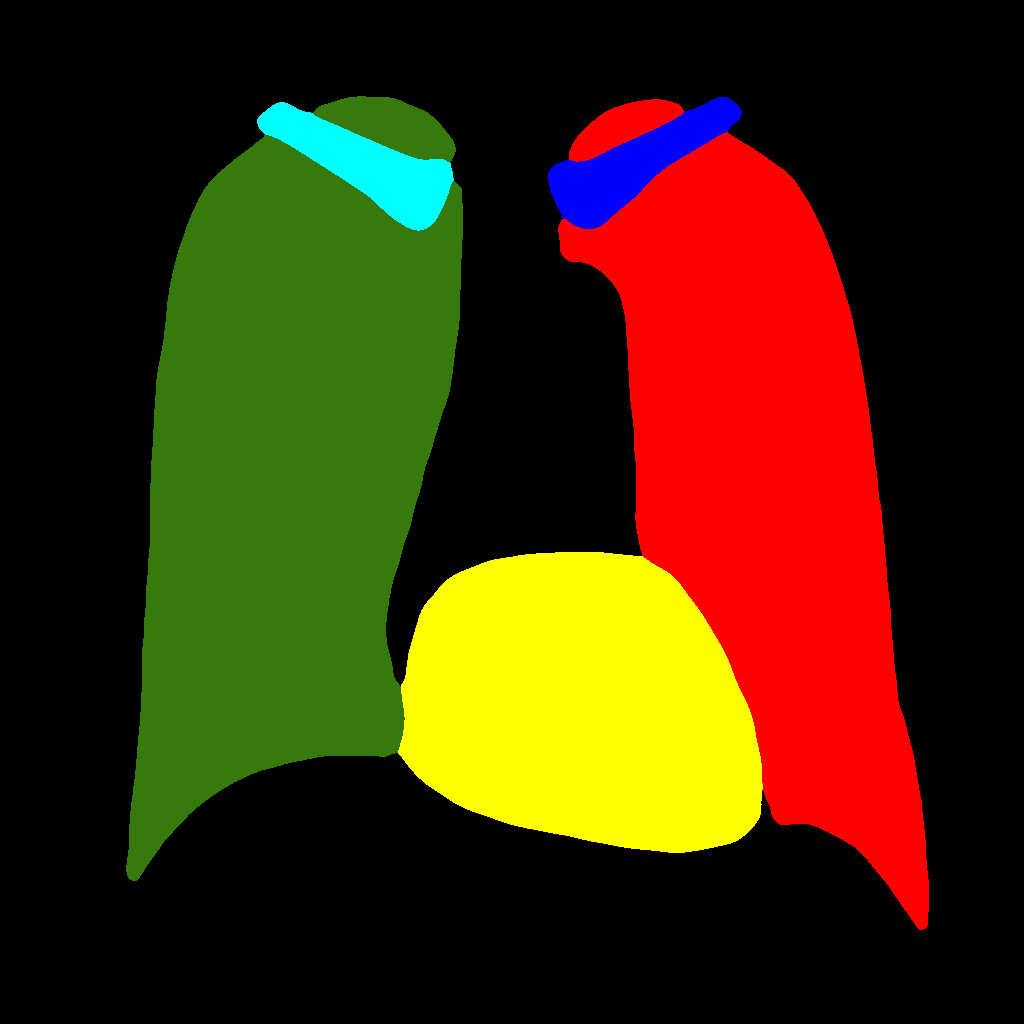

It consists in further subdividing the generation procedure, with a first phase consisting in generating the position and type of the objects that will be generated later, regardless of their shape or appearance. This is obtained by generating label–maps that contain “dots” in correspondence with different anatomical parts (lungs, heart, clavicles). The dots can be considered as “seeds”, from which, through the subsequent steps, the complete label–maps are realized (second phase). Finally, in the last step, chest X–ray images are generated from the label–maps. The exact procedure is described in the following. Initially, label–maps containing “dots”, with a specific value for each anatomic part, are created. The position of the “dot” center is given by the centroid of each labeled anatomic part. The label–maps generated in this phase have a low resolution (), as a high level of detail is not necessary, being the exact object shapes not defined — but only their centroid positions. It should be observed that this also allows to significantly reduce the computational burden of this stage and speedup the computation. The generated label–maps must be subsequently resized to the original image resolution — required in the following stages of generation (a nearest neighbour interpolation has been used to maintain the original label codes) — and translated into labels, which will be finally translated into images, using Pix2PixHD (see Figure 3).